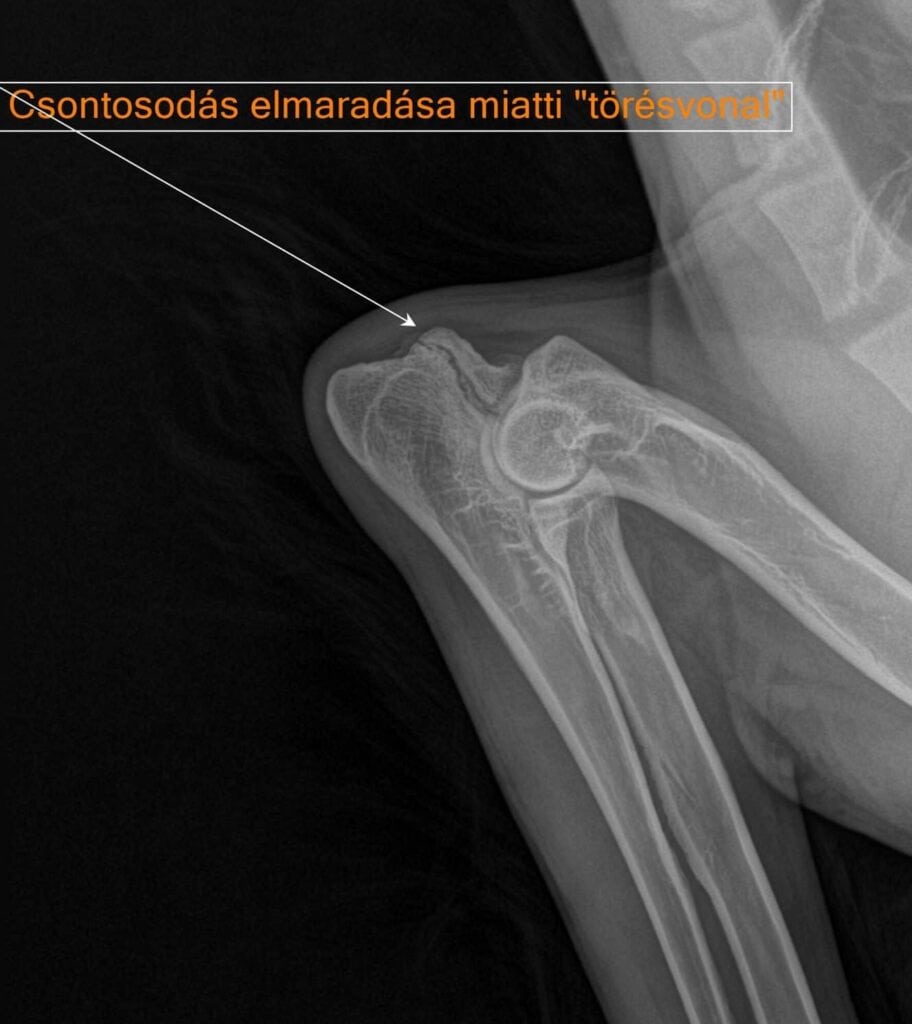

A könyök egy összetett izület. Szűrésekor több szempontot is figyelembe kell venni. Itt látható fiatal német juhászkutya bal könyökén az anconeus nyúlvány elmaradt összecsontosodását látjuk. Ez a könyök diszplázia egyik formája. Összehasonlításképpen mellé tettük a másik oldali, egészséges könyök felvételét. Műtéti ellátás nélkül pár éven belül súlyos sántaság és izületgyulladás várható nála.